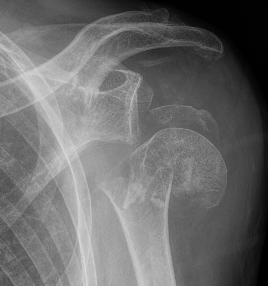

Four part proximal humerus fracture

Rotator cuff arthropathy versus fracture

Paras et al J Shoulder Elbow Surg 2022

- systematic review of rTSA for RC arthropathy v 3 or 4 part fracture

- worse outcome scores and ROM for rTSA in fracture